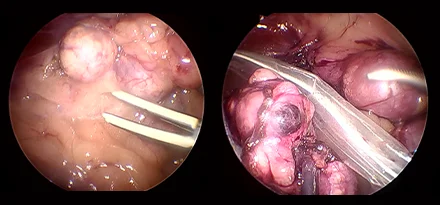

관절경

개,고양이 들은 다양한 관절질환이 존재하고, 복합적으로 존재하는 경우도 빈번합니다.

정확한 진단이 나지 않은 뒤 수술을 하게되면 증상개선이 더디거나 개선이 안될 수 있어, 정확한 진단이 필요합니다.

관절의 경우 X-ray 촬영등으로 진단의 한계가 명확하며, 상위 검사인 CT, MRI 촬영으로도 진단의 한계가 있습니다.

이때 관절경은 내부 구조물들을 직접 시각화 하여 보다 정확한 관절의 상태를 확인하고 진단할 수 있으며, 진단과 치료를 동시에 진행하는 경우도 있습니다. 대표적으로 십자인대단열(CCLR), 골연골염(OCD), 자뼈꿈치돌치유합부전(UAP), 내측관상돌기질환(MCD) 등에 활용될 수있습니다.

관절경 팔꿈치관절(Elbow) 확인

관절경 무릎관절(Stifle) 확인 (반월판 및 십자인대)

* 리본동물의료센터 케이스 사진으로 무단 복제 및 도용을 금지합니다.